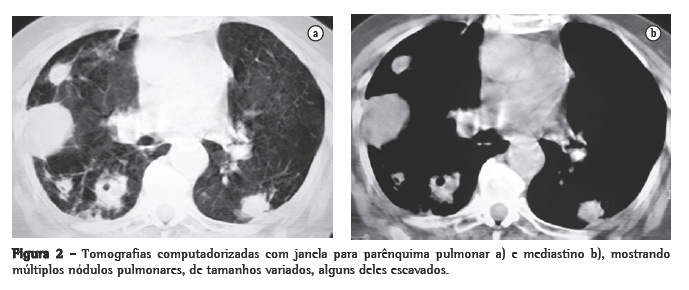

Mulher, branca, 89 anos, com DPOC e relato de bronquiectasias no lobo superior esquerdo há pelo menos 20 anos. O diagnóstico funcional de DOPC foi realizado pelo resultado da relação volume expiratório forçado no primeiro segundo/capacidade vital forçada de 41,2% após o uso de broncodilatador na prova de função pulmonar. Usava diariamente brometo de tiotrópio, b2-agonista de longa duração, associado a corticosteróide inalatório desde setembro de 2004; nas exacerbações agudas, utilizava corticosteróide sistêmico associado a antibiótico de largo espectro. Há 5 dias iniciou quadro de tosse com secreção purulenta, febre de 38 °C, sudorese noturna, prostração intensa, dispnéia e anorexia. Foi prescrito ciprofloxacina por 10 dias, sem melhora clínica, tendo sido internada por 10 dias pelo agravamento do quadro clínico. Nessa primeira internação, a radiografia de tórax mostrava espessamento de paredes brônquicas, pequenas opacidades mal definidas nos lobos superior e inferior direitos e atelectasia com bronquiectasias no lobo superior esquerdo. Foi isolada Klebsiella pneumoniae pela cultura do escarro, e prescrito ceftriaxone, piperacilina/tazobactan. Obteve alta com melhora da febre e da tosse. Em casa, houve recidiva dos sintomas com piora da dispnéia. Realizada radiografia do tórax no domicílio, com aparelho portátil, que mostrou imagens nodulares disseminadas nos pulmões, motivando uma segunda internação (Figura 1). Ao exame apresentava fácies de sofrimento; prostrada; hipocorada; taquipnéica (44 ciclos/min); ­taquicárdica (120 bpm); temperatura axilar, 37 °C; pressão arterial, 120/80 mmHg; e saturação periférica de oxigênio, 84% em ar ambiente. Roncos em ambos os pulmões.

Inicialmente foi prescrita a associação sulfametoxazol e trimetoprima, sem resposta clínica. Foram então prescritas amicacina associada a Imipenem/cilastatina por 15 dias, com excelente resposta clínica e radiológica (Figura 1). Recebeu alta hospitalar com prescrição de sulfametoxazol e trimetoprima por mais 8 semanas.

Nódulos, massas escavadas, derrame pleural, pneumotórax, opacidades em vidro fosco e padrões intersticiais podem também ocorrer.(1,4,5,11) Alguns estudos mostram que, em pacientes HIV positivos, existe um percentual maior de lesões escavadas.(8) A consolidação alveolar nos lobos superiores é muitas vezes confundida com tuberculose pulmonar.(6) Embora as alterações vistas na TC sejam ­semelhantes às das radiografias convencionais, a TC é superior na demonstração da exata localização e extensão das lesões, assim como na diferenciação entre lesões pulmonares e pleurais.(5) No caso relatado, a paciente apresentava imagens nodulares de tamanhos variados, disseminadas por ambos os pulmões, e algumas delas escavadas.